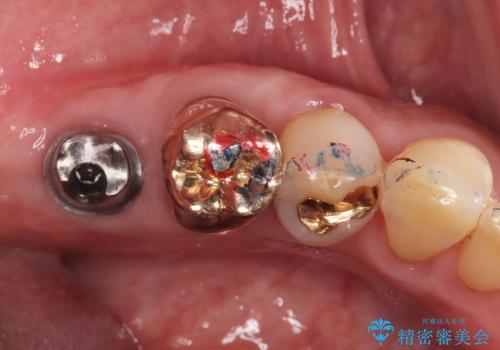

アバットメントの材質は咬合力を考慮しチタン合金にしました。

被せ物はオールセラミッククラウンを入れています。